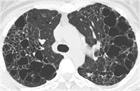

1. 肺LCHの診断には、胸部CT検査(HRCT)は必須である(推奨度1)